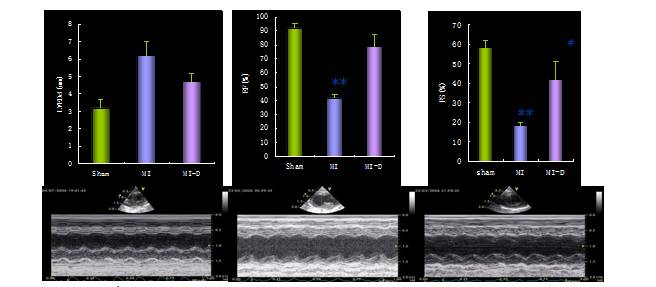

芪苈强心治疗对心脏超声指标的影响

[9]

各组大鼠M型超声心动图代表图形。芪苈强心胶囊治疗组(MI-D组)单相动作电位(MAP)、左室内压(LVSP)及±dp/dt、EF和短轴缩短率(FS)治疗后显著升高;左室舒张末期压LVEDp、左室舒张末期内径LVEDd则显著下降。 *P<0.05, **P<0.01 vs Sham,#P<0.05, ##P<0.01 vs MI。